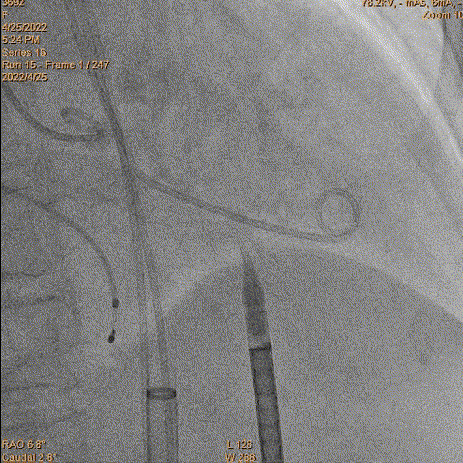

瓣膜再次释放

7、释放完成:第二次释放评估深度合适,缓慢释放脱钩,同轴性良好。撤递送系统,撤抓捕器。

二次评估深度

缓慢脱钩

术后结果:

超声显示支架内径21.5mm,有创压差12mmHg,使用23mm球囊后扩,术后血压115/74mmHg,右无融合处有微量瓣周漏。鉴于血流动力学、舒张压显示良好。没有瓣中瓣的必要。后续保持观察。综合评估,手术达到预期效果,复查通路没问题,结束手术。

23mm球囊后扩

最后造影

复查入路